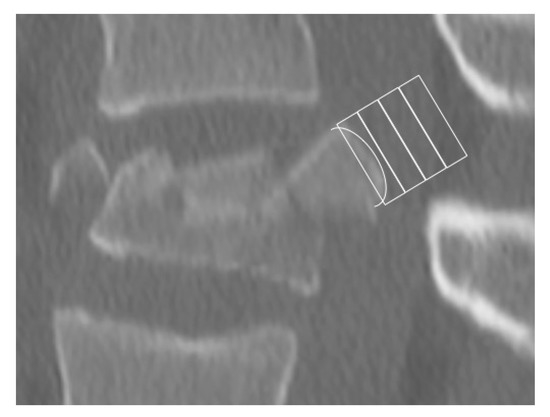

2.2. Morphological Analysis—Bulging